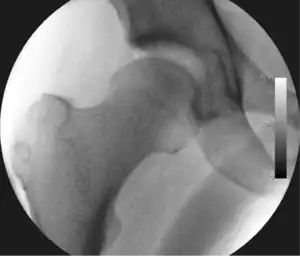

Figure 5. Portal placement under direct vision. The instrument is entering the joint through the hip capsule, between the femoral head (on the left) and acetabular labrum (on the right)

The next step is to insert a fine needle under x-ray guidance into the hip joint. This breaks the 'suction seal' of the joint and allows further distraction if necessary (see fig 4). The surgeon wishes to see the ball move out the socket by approximately 1 cm, so that access to the hip joint can be achieved with minimal risk of damage to the joint surfaces. Most surgeons will inject fluid into the joint at this stage, again to ensure that there is enough space between the ball and socket for safe instrument access. This needle is then removed. The next step is placement of the 'portals', or the small holes made to pass instruments into the joint. This is achieved by again passing a fresh hollow needle into the joint under x-ray control, usually in a slightly different position. The reason for this is so the surgeon can ensure that the needle, and subsequent cannulae do not penetrate and damage the acetabular labrum or cartilage joint surfaces (see fig. 5). Again, surgeons will have their own preferences as to their preferred placement. Through this hollow needle, a long thin flexible guide wire is passed into the joint, and the needle is removed over it, leaving the guide wire in situ. A small cut in the skin is made around the wire, to allow for larger cannulae to be placed over the wire through the portal. The wire therefore guides the larger cannulae into the joint. The most common external diameters of cannulae used are between 4.5 and 5.5 mm. Once the surgeon is satisfied that the cannula is in the correct position, by a combination of feel and x-ray guidance, the guide wire can be withdrawn. Once the first portal is correctly placed, any further portals may be created once the camera is in position, to ensure that they are placed with minimal risk to the joint surfaces. This process can be repeated to gain as many points of entry to the hip joint as the surgeon requires, normally between two and four. Certain of these entry points will be used for the viewing arthroscope and others for operating instruments.